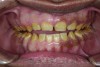

Figure 2. Preoperative 1:2 retracted frontal view.

Figure 2

A thorough clinical examination and analysis were carried out to assess the esthetic and functional problems of the patient (Figure 2 through Figure 7). The medical history was non-contributory, except for mild leukoderma. Temporomandibular joint (TMJ) function was within normal range.

Mounted study casts were used to evaluate occlusion. The relevant findings were as follows2: Facial analysis revealed a canted maxillary occlusal plane and canted dental midline. Dentolabial analysis showed that the maxillary incisors were not adequately visible during repose; it also revealed a reverse smile line, as well as a wide smile showing 12 teeth. Results from the phonetic analysis were that “F” and “V” sounds revealed upper incisal shortening, “M” and “S” pronunciation disclosed a diminished vertical dimension of occlusion (VDO), and “E” sounds showed severe shortening of incisors. Dental analysis revealed thick biotype, asymmetry and inappropriate location of gingival levels and zenith, incorrect axial inclinations, a displeasing width-to-length ratio, and pitted surfaces on most teeth. Interproximal decay was evident on several posterior teeth, as revealed by radiographic analysis. Finally, occlusal examination indicated discrepancy between maximum intercuspation (MIP) and centric relation (CR) as well as a lack of anterior guidance/posterior disclusion.